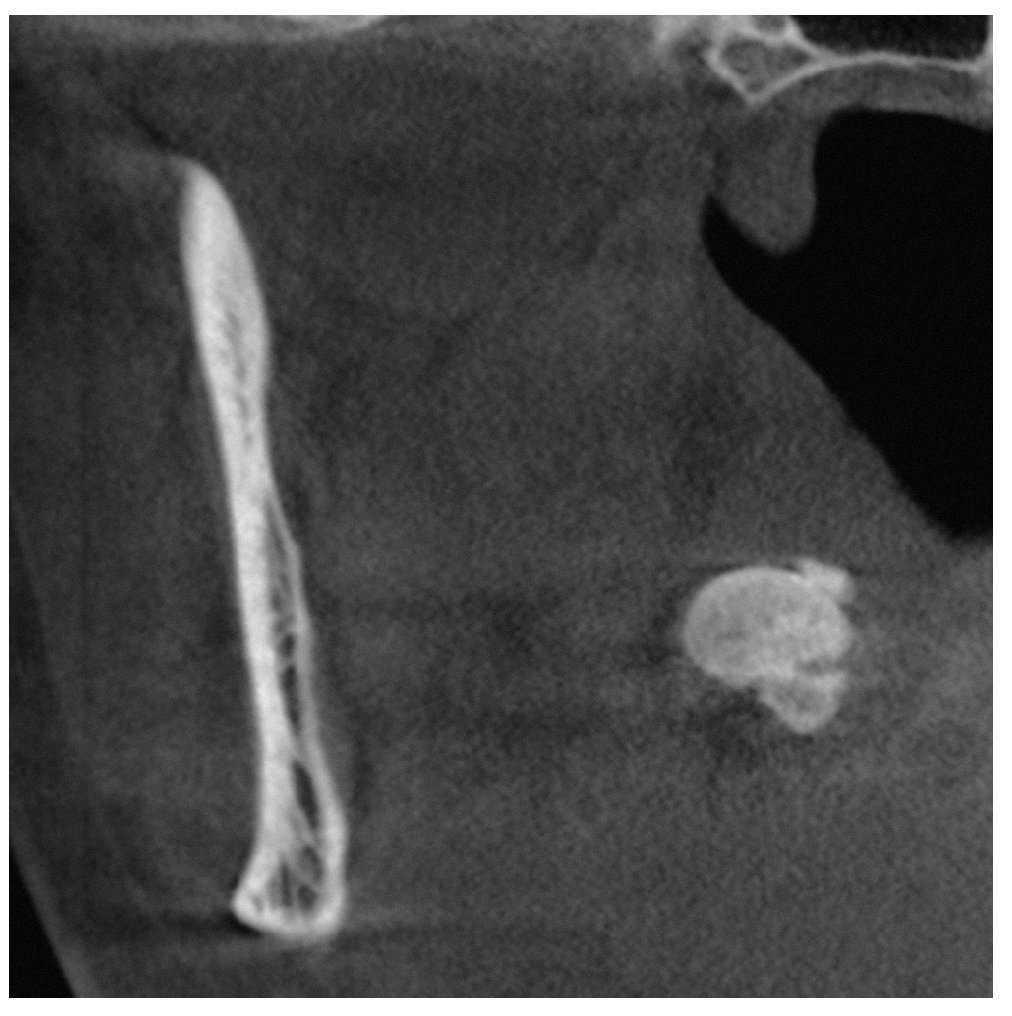

Se obtuvo una tomografía volumétrica digital dental para completar el estudio diagnóstico. En la tomografía destacó a 1,5 cm en medial de la rama mandibular derecha una masa redondo-ovalada, hiperdensa y bien delimitada con un tamaño de aproximadamente 12 x 10 mm localizada en los tejidos blandos parafaríngeos (figs. 2 a 4). De este modo se descartó con certeza la presencia de un sialolito.

Figura 2. Tomografía volumétrica digital dental: plano axial.

En la faringe existen diversos «islotes» de tejido linfático que se denominan amígdalas o tonsilas. Las zonas parafaríngeas de las mismas corresponden a las amígdalas palatinas. Las infecciones recidivantes de las vías respiratorias altas (bronquitis, laringitis) pueden provocar abscesos crípticos en el tejido linfático que, más adelante, pueden calcificarse. Como resultado de su ubicación, en las radiografías se suelen proyectar sobre la rama mandibular y se visualizan a menudo como imágenes radioopacas de pequeño tamaño parecidas a salpicaduras calcáreas. Por el contrario, las calcificaciones de mayor tamaño, como las de este caso clínico, son más bien raras y suelen corresponder a un cálculo amigdalino o tonsilolito.